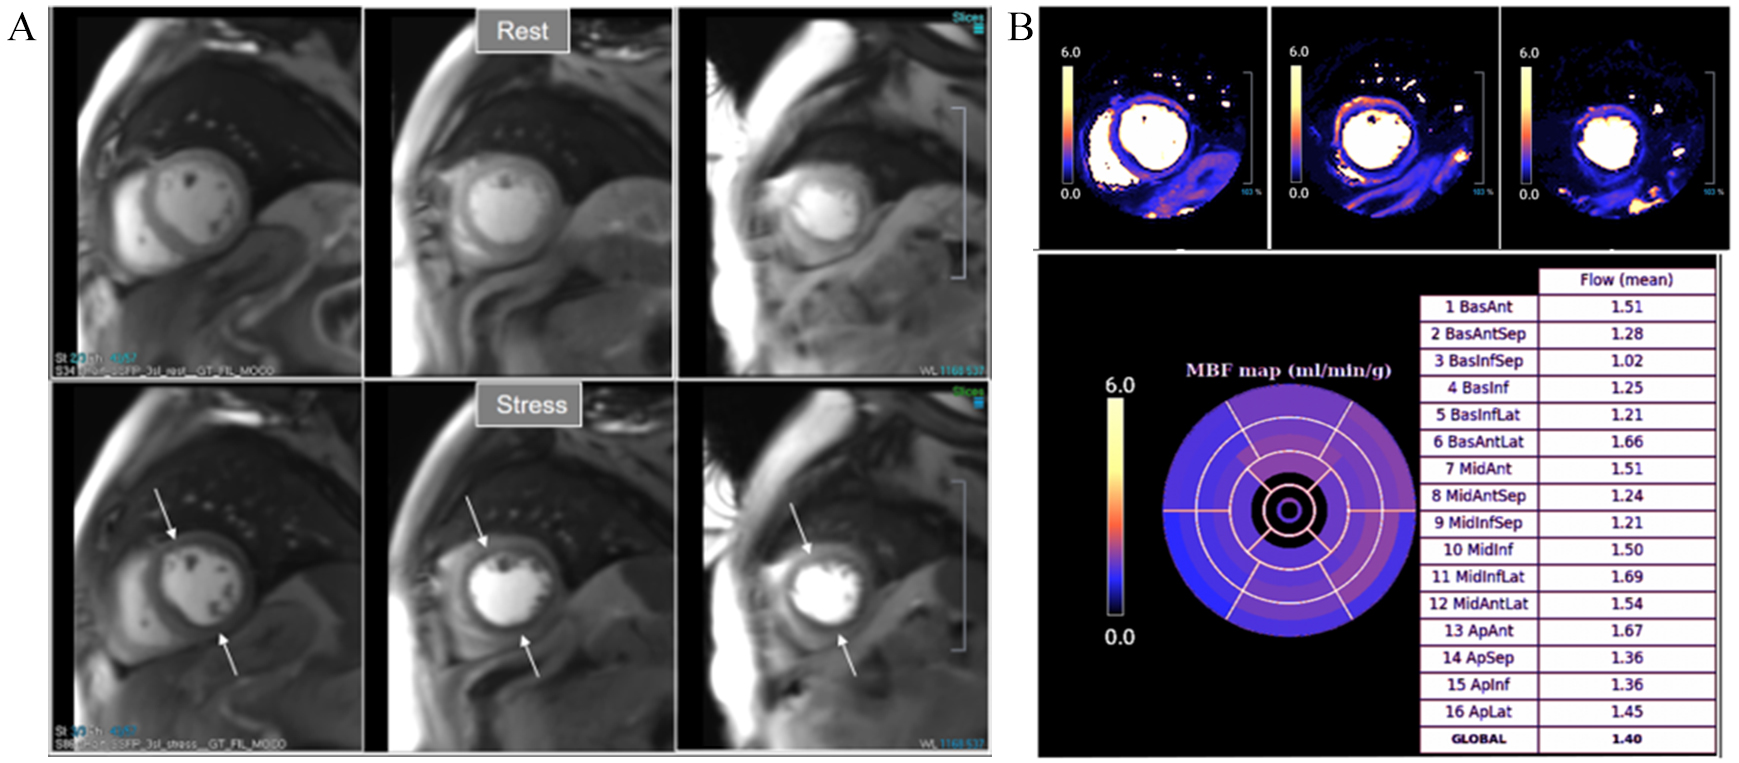

Fig. 34.Severely abnormal perfusion mapping. (A) Rest and stress perfusion studies in a patient with severe advanced multivessel CAD showing a global subendocardial and partially transmural inducible defect (arrows). (B) Perfusion mapping showing extremely reduced values of stress MBF indicating multivessel obstructive disease.